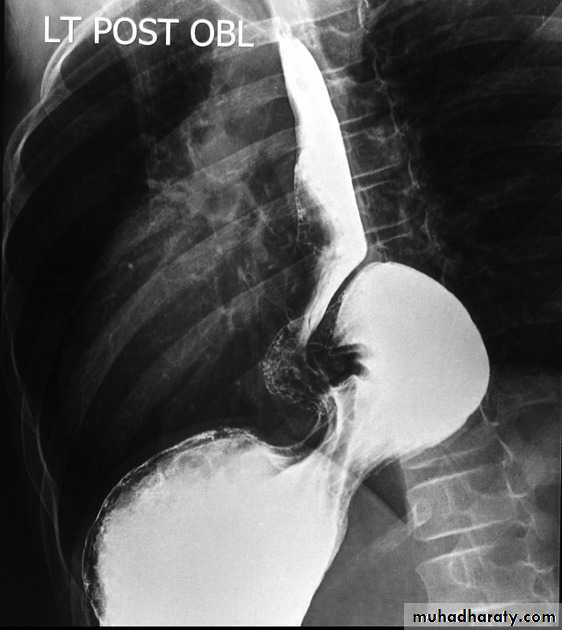

Webs

Majority protrude from anterior esophageal wall

short, thin web (arrows) with minimal intraluminal extension.